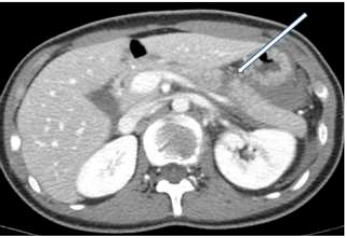

73.中年男性車禍傷患主訴上腹部劇痛,血壓呈現穩定狀態。電腦斷層檢查如附圖。箭頭所指之異常最可能是下列那一項初診斷? (A)liver laceration (B)colon laceration (C)pancreas laceration (D)mesentery laceration